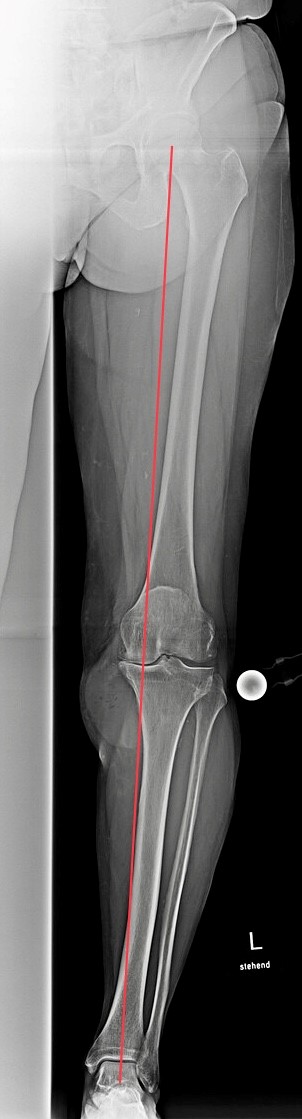

Die Blickdiagnose bestätigte sich durch die Röntgen- und MRT-Aufnahmen: eine ausgeprägte Arthrose des Kniegelenks mit Schwerpunkt der Knorpelschädigung auf der Innenseite. Folgen der fortgeschrittenen Gelenkschädigung waren die zunehmende O-Bein-Fehlstellung und die Ausbildung eines sehr großen Ganglions (mit Gelenkflüssigkeit gefüllte Raumforderung).

Nachdem die nicht operativen Therapiemaßnahmen (Krankengymnastik, korrigierende Einlagen, Spritzentherapie) ausgeschöpft waren und die Lebensqualität anhaltend beeinträchtigt war, wurde die Patientin über die Option eines künstlichen Kniegelenks (KnieTotalEndoProthese = KTEP) informiert. Mithilfe eines Oberflächenersatzes (Typ „Doppelschlitten“) konnte die abgenutzte Knorpeloberfläche überkront und gleichzeitig die korrekte Beinachse wiederhergestellt werden. Das Ganglion wurde über den gleichen OP-Zugang erfolgreich entfernt.